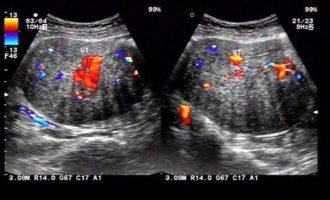

子宫环境检查(B超 & 宫腔镜)

一个健康的“土壤”(子宫)是胚胎着床的必要条件。阴道B超 可以检查子宫和卵巢的形态,排查子宫肌瘤、子宫内膜息肉、卵巢囊肿等可能影响怀孕的器质性病变。如果B超提示子宫内膜异常或有反复流产史,医生可能会建议进行宫腔镜检查,这是一种微创手术,能直接观察宫腔内部情况,并对发现的息肉、粘连等问题进行同步处理。